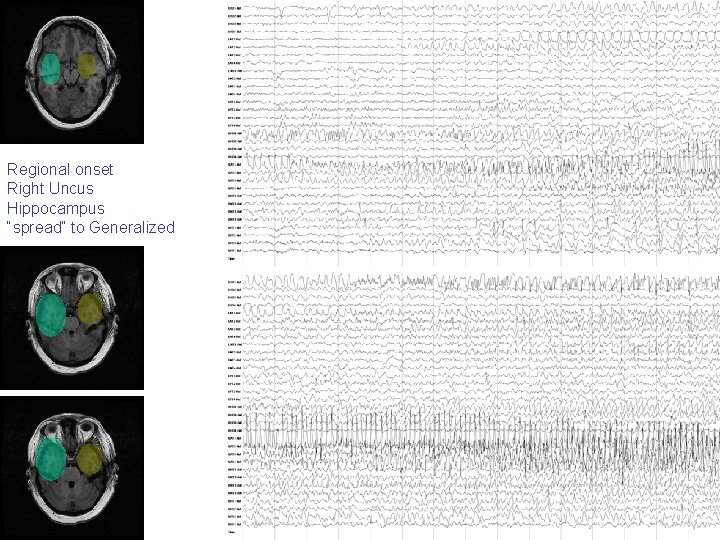

An individual patient may have more than one morphology and/or localization of seizure onset Next seizures all from same patient, now seizure free >1 year after right anterior temporal lobe resection

Five different seizure onsets recorded from intracranial depth electrodes in one patient over 24 hours

Regional onset Right Uncus Hippocampus “spread” to Generalized